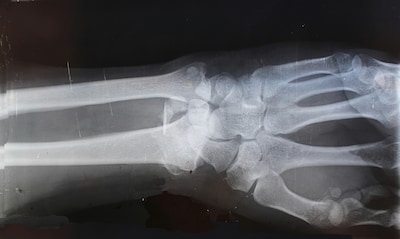

Chinese onderzoekers beweren een revolutionaire ‘superlijm’ voor botten te hebben ontwikkeld. Met de bottenlijm kunnen breuken, die normaal gesproken maanden nodig hebben om te genezen, binnen enkele minuten worden hersteld.